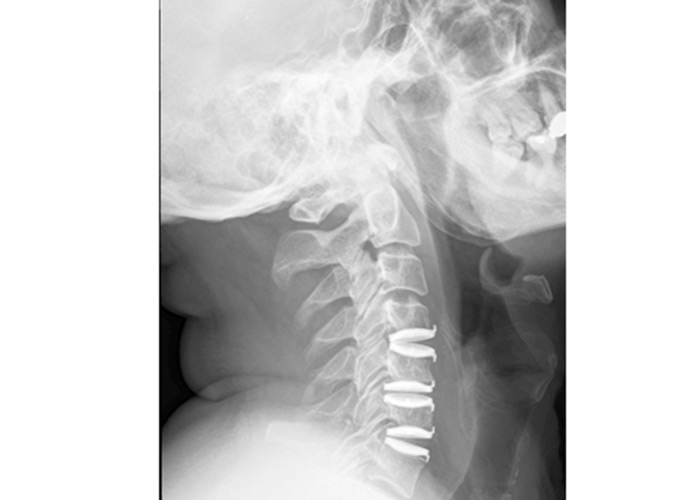

• Resonancia Magnética Cervical: voluminosas hernias discales cervicales C4-C5, C5-C6 y C6-C7 con estenosis del canal espinal central más acusado en C5-C6 y mielopatía cervical C5-C6.

mielopatia-cirugia-de-columna-vertebral-en-madrid

Se comenzó por el nivel C6-C7, se completó discectomía, resección de los osteofitos óseos posteriores y del ligamento vertebral común posterior. Se liberó ambos forámenes C6-C7, bilateralmente, implantándose prótesis de Bryan (Medtronic). Se realizó nuevamente la técnica en los niveles C5-C6 y C4-C5, liberando ambos forámenes y voluminoso osteofito posterior del borde inferior de C5.